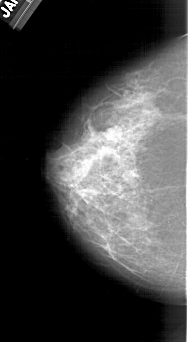

A_1382_1.LEFT_MLO

A_1382_1.LEFT_CC

LEFT_CC LINES 5461 PIXELS_PER_LINE 3001 BITS_PER_PIXEL 12 RESOLUTION 43.5 NON_OVERLAY

LEFT_MLO LINES 6106 PIXELS_PER_LINE 3106 BITS_PER_PIXEL 12 RESOLUTION 43.5 NON_OVERLAY